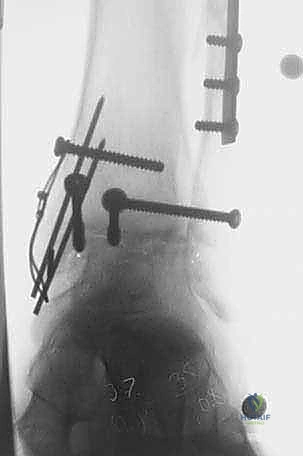

* Fluoroscopic Confirmation: Before making any cuts, confirm the placement and size of the cutting block with intraoperative fluoroscopy in AP, lateral, and mortise views. This is a non-negotiable step to ensure accuracy and prevent malalignment.

- Fluoroscopic Confirmation of Apposition and Anatomy:

<a href="/media/hutaif_opertive/hutaif-ch67-total-ankle-she-p4058-0bb

Additional Intraoperative Imaging & Surgical Steps